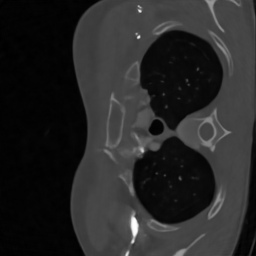

Computerized tomography

We consider parallel beam X-ray computerized tomography. It consists in probing line integrals of an object along a set of parallel lines that may be rotated and shifted. In this application the parameter represents the angles and shift at origin of the lines. The problem becomes blind if the object to image moves during the scan.

We trained the network using iterations using the ImageNet database. We initially used the Lung Image Database Consortium [7] database, but realized that it contains many improper slices (high noise, streaking artifacts, little contents…). We evaluated the algorithm on a curated version called LoPoDaP [58], containing less artifacts. The test dataset contains 4096 images.

As the blind inverse problem (5) requires differentiating the operator with respect to its parameters , we cannot use standard GPU-based libraries to compute the Radon transform [76]. We thus resorted to an homemade implementation that relies on a NUFT through the Fourier slice theorem. In order to reduce the important numerical cost and energy consumption of the experiments with CT reconstruction, we downsized the images to .

6.3.2 Computerized tomography

In this application, a model mismatch might occur due to the motion of a patient in the scanner. Correcting this mismatch is essential. Not accounting for it, can result in severe artifacts including some details loss and blur as can be seen in Fig. 6.

To identify the forward model, we ran the Adam optimizer on the parameters for iterations. In this application, represents the angle of the parallel shots and their shift at origin. All the reconstruction methods are able to significantly reduce the model mismatch, passing from maximal angles shifts of 7 degrees to less that 1 degree. Similarly, the shifts at origin are reduced from more than a pixel to about pixel. The reconstruction performance is significantly improved after estimating the forward model with PSNR increases of dB and more. The neural network trained on a family provides the best reconstruction results on this example.

Similarly to blind MRI, Table 4 shows that the “deep unrolled prior” method consistently provides good estimates of the forward model and significantly improves the reconstruction quality for the CT experiments.

| Test | Recon. PSNR with (dB) | Recon. PSNR with estimated (dB) | Shift err. | Angle err. |

| 1 | 28.16 | 33.91 | 0.52 | 0.25 |

| 2 | 30.63 | 38.17 | 0.66 | 0.31 |

| 3 | 27.10 | 32.47 | 0.72 | 0.33 |

| 4 | 26.93 | 34.09 | 0.36 | 0.28 |

| 5 | 26.81 | 34.26 | 0.42 | 0.22 |

| 6 | 27.52 | 37.89 | 0.62 | 0.12 |

| 7 | 29.68 | 37.21 | 0.57 | 0.34 |

| 8 | 27.44 | 37.16 | 0.68 | 0.40 |

| 9 | 26.89 | 35.84 | 0.92 | 0.38 |

| Avg | 27.91 | 35.67 | 0.61 | 0.29 |